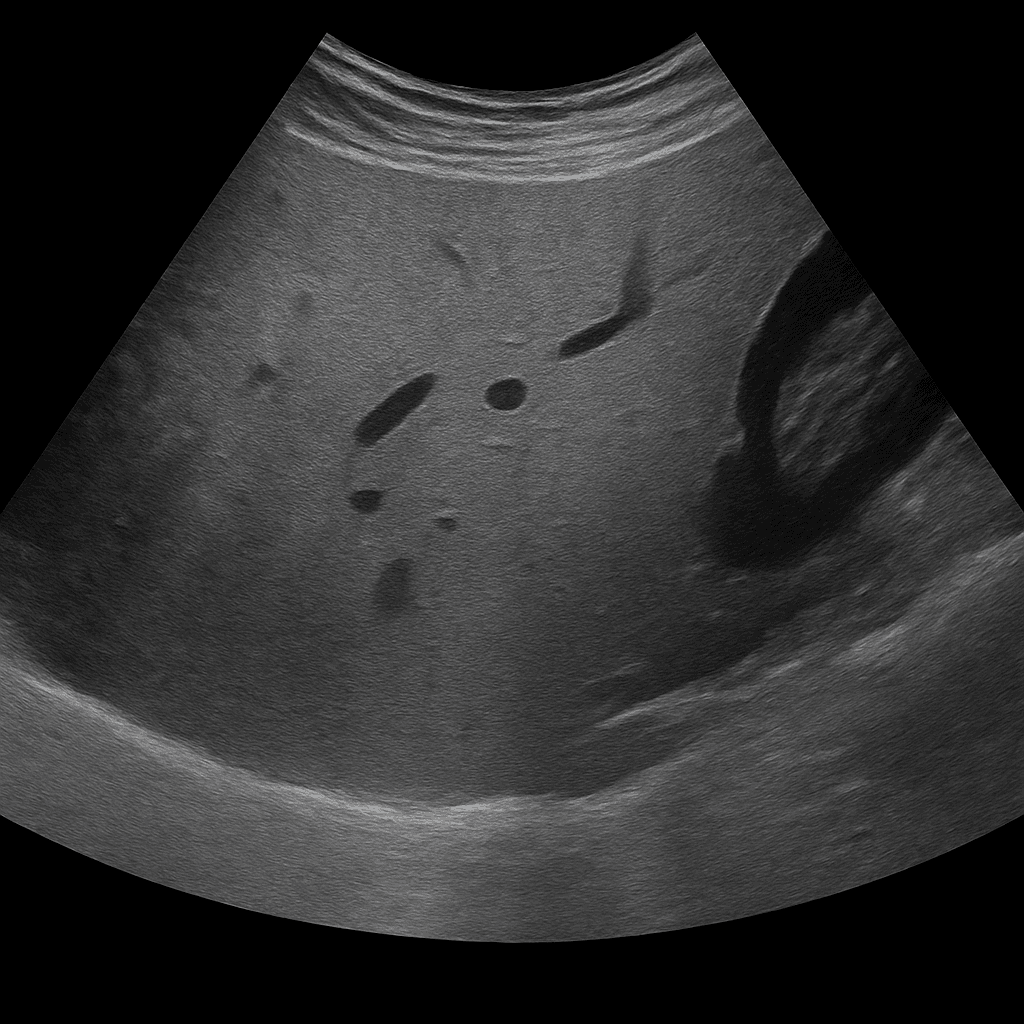

Ultraljudsundersökning av levern används för att undersöka leverns storlek, struktur och kärlflöde. Undersökningen utförs av specialistläkare inom radiologi och ger detaljerade bilder i realtid som visar förändringar som kan tyda på fettlever, inflammation, cystor, tumörer eller cirros. Ultraljud lever är ofta förstahandsmetoden vid utredning av avvikande leverprover eller bukbesvär kopplade till levern.

Till skillnad från MR eller DT, som används för detaljerad kartläggning av vävnadsförändringar och blodkärl, är ultraljud den primära metoden för att bedöma leverns struktur, fettinlagring, kärlflöde och volym. Ultraljud kan snabbt påvisa avvikelser utan strålning och används ofta som första steg i leverdiagnostiken.

Undersökningen utförs medan du ligger på rygg eller lätt på vänster sida. En gel appliceras på huden och läkaren för ultraljudsproben över området under höger revbensbåge. Undersökningen tar vanligtvis 15–20 minuter. För bästa bildkvalitet bör du vara fastande i cirka 4–6 timmar innan, eftersom mat och luft i tarmen kan påverka bildens tydlighet.